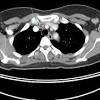

A ct scan is one of the most frequently utilized exams to detect cancer and to show things such as a tumor's shape and size.

Before a pet/ct scan, an iv that injects a small amount of a radioactive substance will be placed into one of your veins. It also helps doctors predict how well you will recover.find the right place for a biopsy.plan A pelvic ct scan can be used to detect several types of cancer. When the doctor knows this, they can choose the best course of treatment and maybe even predict your chances of recovery. The scan lets them:learn the cancer's stage. However, they are also scanning my thorax. I performed an scope examination of her esophagus and confronted a huge cancer occupying the lower portion of her esophagus. A ct scan can help detect a wide range of abnormalities or disease, including cancer, in any part of the body. Each picture created during a ct procedure. Further, its diagnostic reach can go beyond the bone. You are encouraged to drink clear liquids. Do ct scans detect breast cancer? Learn more about it on our blog.

Ct scans can help doctors: If you have a large breast cancer, your doctor may order a ct scan to assess whether or not the cancer has moved into the chest wall. This substance is often called a tracer, because it helps reveal cancer in the body. The scan lets them:learn the cancer's stage. Computed tomography scan, ct scan, cat scan, and spiral or helical ct. 234 views answered >2 years ago Before the scan, you will either drink a liquid dye or be given an injection of dye into a vein in your arm. Breast cancer affects over 200,000 women each year. A pelvic ct scan can be used to detect several types of cancer. Contrast medium is a dye that helps body tissues show up more clearly on the scan. In contrast with bone scans, which are only able to detect bone metastases, pet/ct has the advantage of concurrently imaging other common sites of breast cancer metastases such as the liver and lungs, says lead author patrick morris, a breast cancer specialist at memorial sloan kettering. You are encouraged to drink clear liquids. This helps determine whether or not the cancer can be removed with mastectomy.

In general breast cancer can be detected on a routine chest ct scan regardless of if contrast media is used or not. Several types of cancer can form in the breast, making it the second most common cancer that affects american women. These scans expose you to more. Before a pet/ct scan, an iv that injects a small amount of a radioactive substance will be placed into one of your veins. Long story short i have a ct scan with contrast on 1st june to look for cancer in the abdominal cavity.